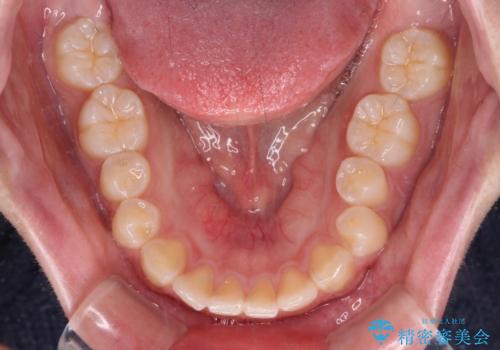

- 出っ歯と口の閉じにくさ、デコボコを気にして来院された患者様です。

口元の突出感を改善するため、上下左右第一小臼歯4本の抜歯を行い、ワイヤー装置による矯正治療を行うこととしました。

抜歯矯正を行ったことで、顎先のつっぱり感や口元の閉じにくさを解消することができました。